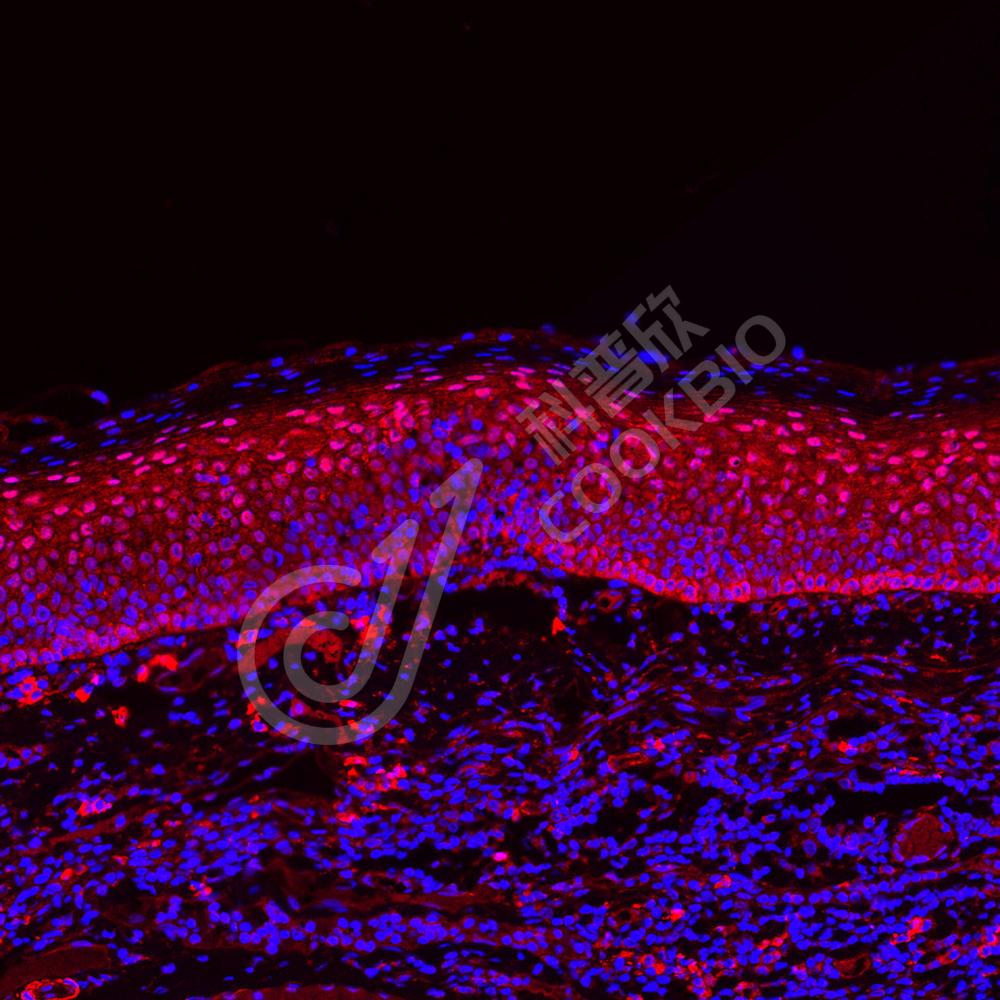

IHC/IF 免疫组织化学/免疫荧光

物种:小鼠,大鼠

稀释比:1:500-1:2000

阳性样品:肺

IHC检测HSPA6蛋白(货号 K1334980).

样品: 大鼠肺, 4%多聚甲醛 (货号KSG1101) 固定12-24小时.

抗原修复: 柠檬酸抗原修复液(干粉, pH 6.0) (KSG1201), 98℃, 20分钟.

—抗: 1: 1300稀释, 4℃ 孵育过夜.

二抗: S-vision免疫组化多聚二抗(山羊抗兔),即用型 (货号KB3906), 室温孵育20分钟.